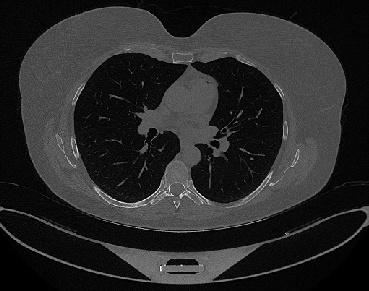

It should be mentioned that for explainability purposes [7, 8, 9], an anchor set was generated for the COV19-CT-DB database [5]. This included 11 anchors, each representing a respective 3-D CT scan obtained through an appropriate clustering procedure. Figure 2 shows a series of slices from a COVID-19 case, whereas Figure 3 shows a series of slices from a non COVID-19 case.